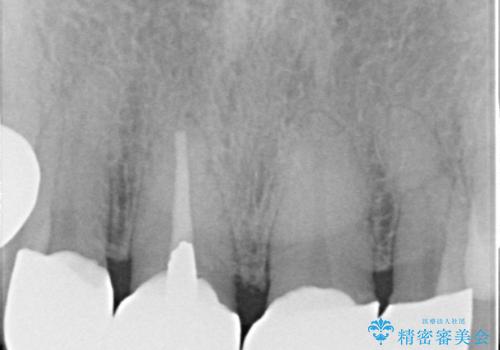

- 矮小歯である前歯がしみるとのことで来院された患者様です。

上顎前歯の歯肉ラインにエナメル質の欠損が認められ、そこが原因で冷たいものがしみている状態でした。

歯の大きさが小さいこと、隣の歯や反対側のセラミッククラウンの境目が見えていることなどから、前歯4本あるいは6本に対して、オールセラミッククラウンによる補綴治療をご提案しました。